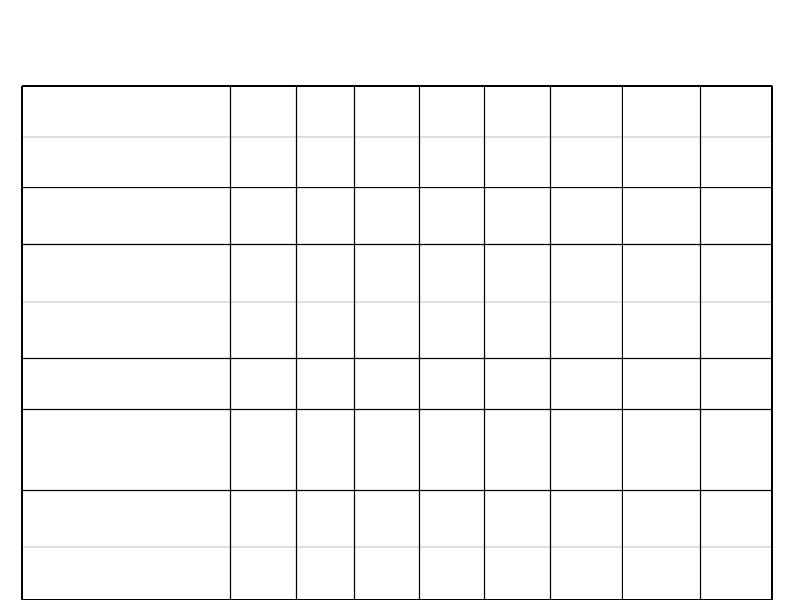

Время удвоения лимфоцитов менее 6 месяцев Время удвоения лимфоцитов более 6 месяцев Стадия на момент диагноза III – IV / C (Rai / Binnet) Возраст менее 65 лет I – II / A Возраст более 65 лет ZAP-70 < 20% Соматическая мутация (-) Соматическая мутация (+) 17 p делеция (p 53 мутация), 13 q делеция 11 q делеция, 12 q трисомия CD 38 (+) CD 38 (-)

Факторы, влияющие на выбор терапии больных ХЛЛ

Тактика лечения больных ХЛЛ на постремиссионном этапе